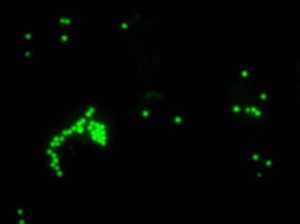

Микроскопическая оценка фагоцитоза латексных частиц

Микроскопия в проходящем свете, 100×

Флуоресцентная микроскопия, 100× (поглощение - 495 нм, эмиссия - 517 нм)